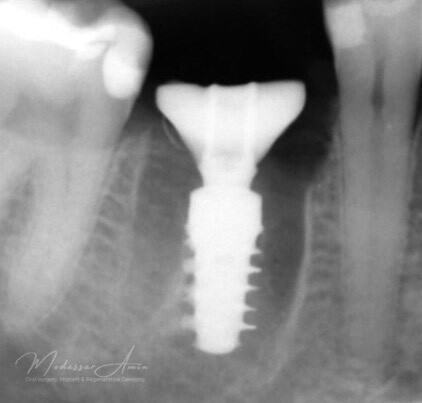

Kontrollröntgen SSA

CBCT röntgen